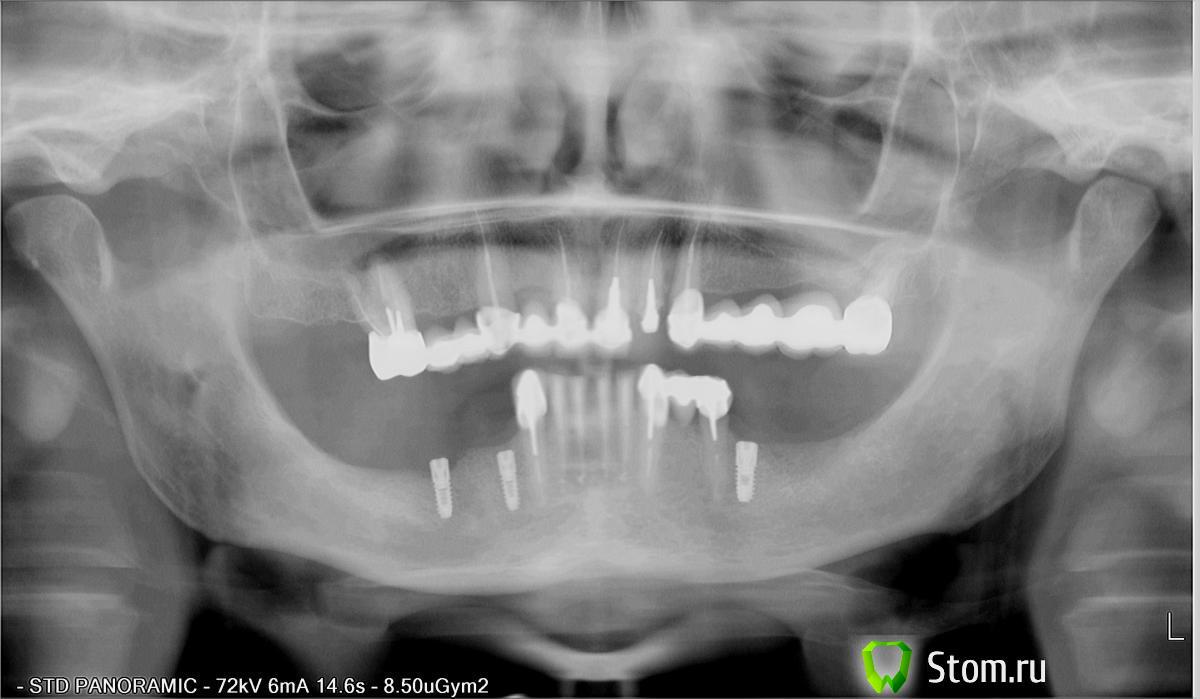

VITASVIR1979 Опубликовано 14 марта, 2012 Поделиться Опубликовано 14 марта, 2012 Около 7 лет назад пациент протезировался у меня мостовидным протезом ("подковой")в/ч и мостовидным протезом и кламмерным бюгелем н/чОколо года назад с ним произошло ДТП,в результате-от удара сломался верхний мост(лопнуло соединение в области 23,24 d-s,и многочисленные сколы керамики)...и пришел в негодность бюгельный протез н/чВ результате,после ряда безуспешных починок,принято было решение протезировать н.ч несъёмной конструкцией(по желанию пациента),с опорами на имплантыа в/ч-мостовидным протезом в переднем отделе и бюгельным- в боковых( 27 d -под удаление)в процессе также выяснилось,что есть трещина продольная на клыке(23)...((Пациент хочет поставить еще 2 импланта на в/ч в области 23-24,чтобы не прибегать к синуслифтингу....В общем,друзья,посоветуйте, как быть...ОРТОПАНТОМОГРАММА И СХЕМА прилагаются....Спасибо)) Ссылка на комментарий

pit Опубликовано 15 марта, 2012 Поделиться Опубликовано 15 марта, 2012 ............Пациент хочет поставить еще 2 импланта на в/ч в области 23-24,чтобы не прибегать к синуслифтингу....В общем,друзья,посоветуйте, как быть... План конечно не очень. Но для того чтобы его реализовать необходимо правильно оформить документы) или обозначить как временное протезирование.И я бы еще 47 зуб бы доставил, а то 44 и 46 -короткие и тонкие. Кстати, почему тонкие импланты установили под мостовидный протез, а не для каждого зуба? 1 Ссылка на комментарий

VITASVIR1979 Опубликовано 17 марта, 2012 Автор Поделиться Опубликовано 17 марта, 2012 Спасибо!Сам понимаю,что не особо-то план...поэтому и здесь)) на КТ размеры костной ткани не позволяют дальше произвести имплантацию (очень узкий альвеолярный гребень),а между 44 и 46- выходное отверстие (подбородочное).... Ссылка на комментарий